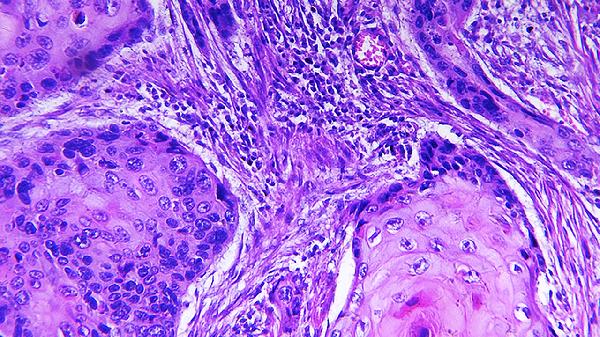

腦腫瘤分為膠質(zhì)瘤、腦膜瘤和垂體瘤等類型。腫瘤壓迫周圍神經(jīng)組織可引發(fā)進(jìn)行性加重的頭痛、視力下降或肢體抽搐。垂體瘤可能導(dǎo)致激素分泌異常,出現(xiàn)閉經(jīng)或肢端肥大。診斷依賴頭顱MRI增強(qiáng)掃描,治療需根據(jù)病理類型選擇手術(shù)切除,術(shù)后可能需輔助放療或替莫唑胺膠囊化療。